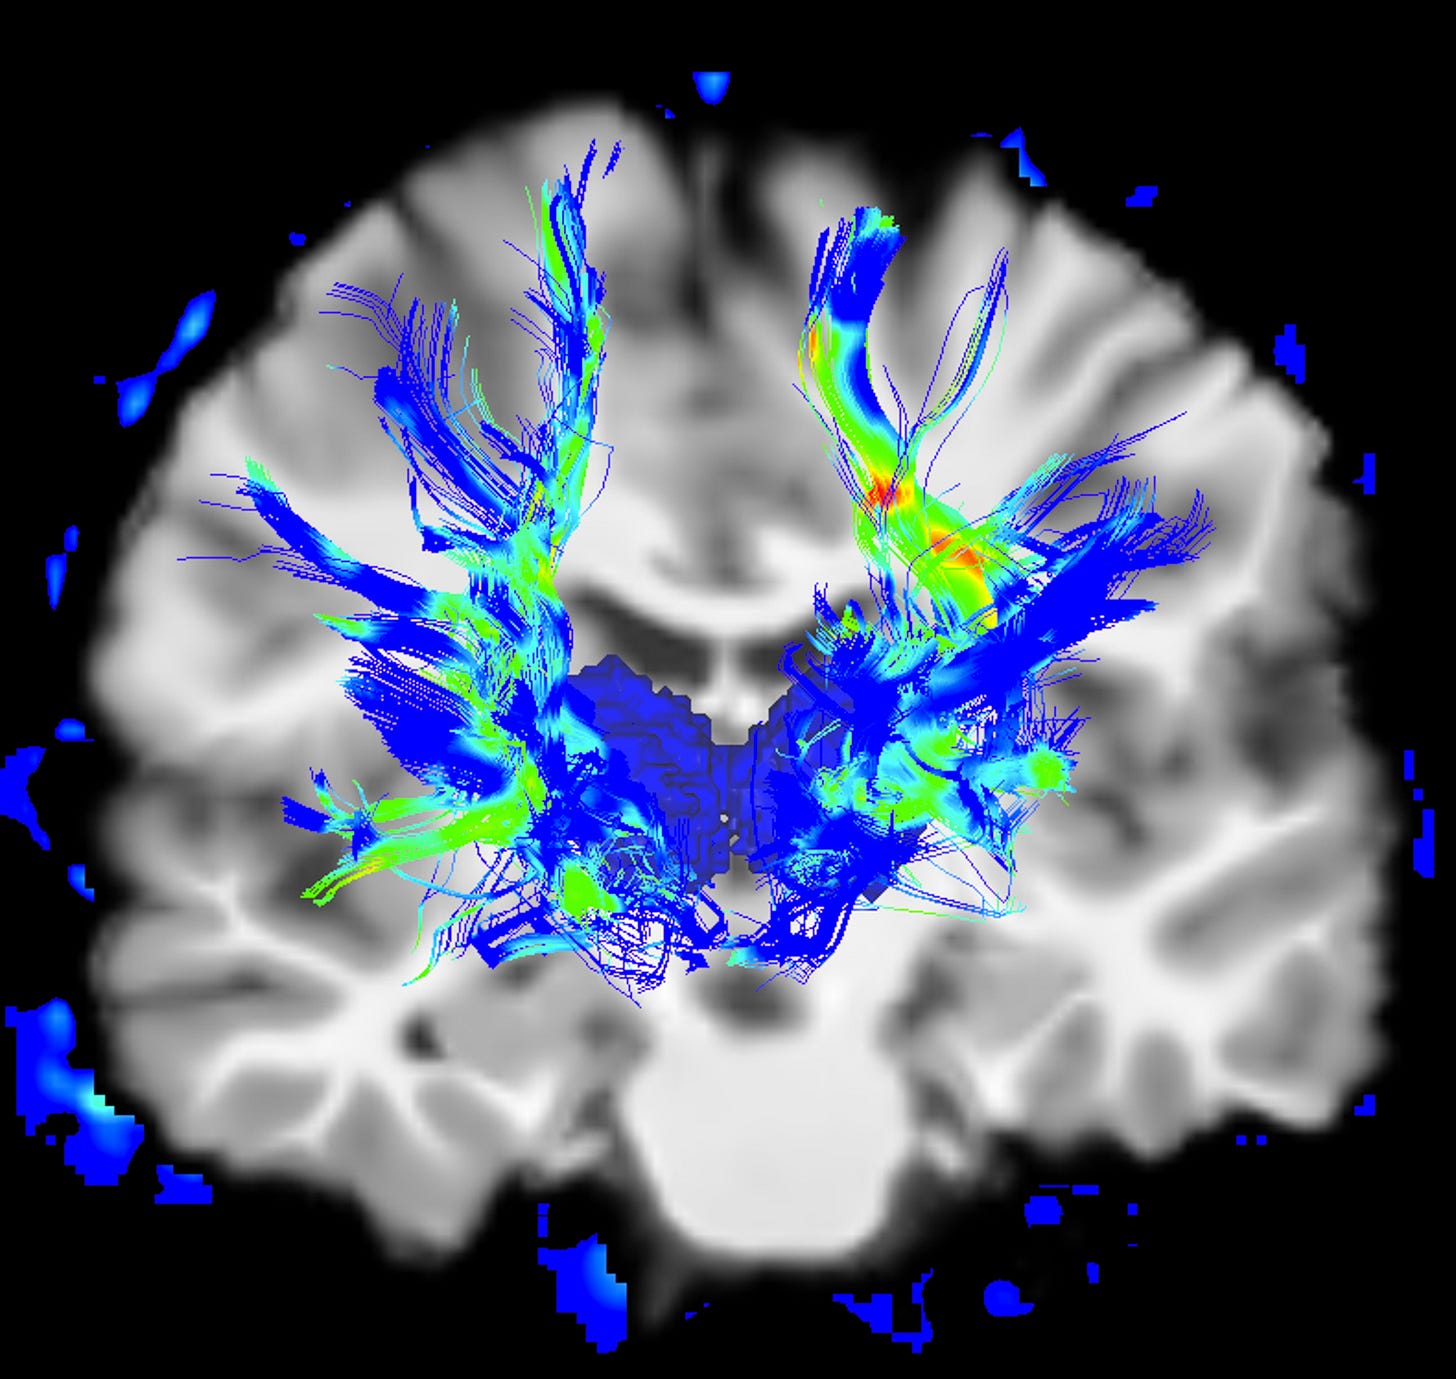

Second, a post by Imperial College about something close to my heart, the Parkinson’s Brain Bank at London’s Hammersmith Hospital. If we are ever to understand the disease and find a cure, then the research done at the brain bank may be our best hope. The Imperial post includes my report two years ago for BBC Breakfast in which I make the decision to leave my own brain for research.